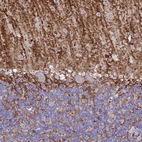

Immunohistochemistry analysis in human cerebral cortex and liver tissues using AMAb90537 antibody. Corresponding AQP4 RNA-seq data are presented for the same tissues.